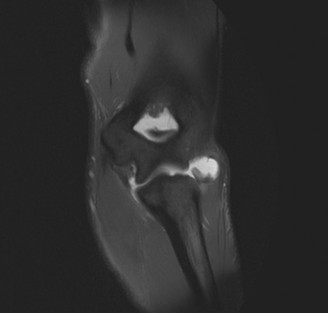

The patient undergoes conservative management consisting of rest, anti-inflammatory medications, and physical therapy. After six months, he is still not able to return to play and has progressively worsening symptoms with attempted throwing. He has a moderate elbow effusion as well as a 20-degree flexion contracture. An elbow MRI arthrogram is obtained and shown (Fig. 2–112). He elects to proceed with elbow arthroscopy. Intraoperative arthroscopic images are shown (Figs. 2–113 and 2–114).

Figure 2–112

Figure 2–113

Figure 2–114